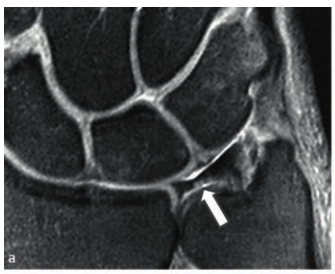

특히 2024년 Schmitt 등의

연구에서 강조한

'중심와 층(foveal lamina)'을

주목해야 합니다.

이 부위는 TFCC의 뿌리에 해당하고

척골 뼈의 깊숙한 곳(fovea)에

붙어 있다고 말씀드렸죠.

0.2mm 단위로 영상을 만들어주는

고해상도 인플레인 3.0T MRI 검사가

필수적인 것이죠.